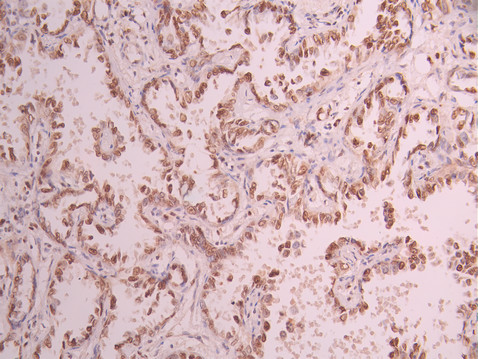

IHC image of CSB-RA799971A0HU diluted at 1:100 and staining in paraffin-embedded human lung cancer performed on a Leica BondTM system. After dewaxing and hydration, antigen retrieval was mediated by high pressure in a citrate buffer (pH 6.0). Section was blocked with 10% normal goat serum 30min at RT. Then primary antibody (1% BSA) was incubated at 4°C overnight. The primary is detected by a Goat anti-rabbit polymer IgG labeled by HRP and visualized using 0.05% DAB.